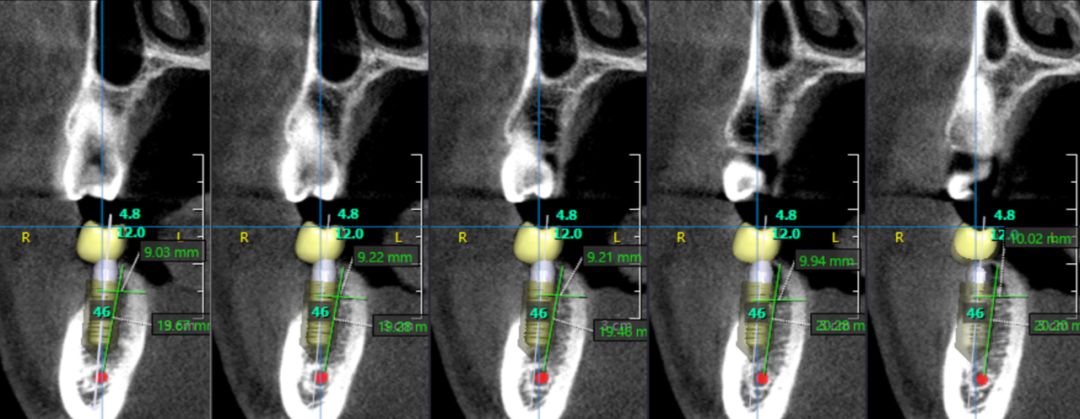

OnDemand 3D后處理軟件直接模擬真實(shí)種植場(chǎng)景,更有骨密度精確測(cè)量,醫(yī)患溝通更直觀,手術(shù)更安全,患者更信任。

骨密度精確測(cè)量